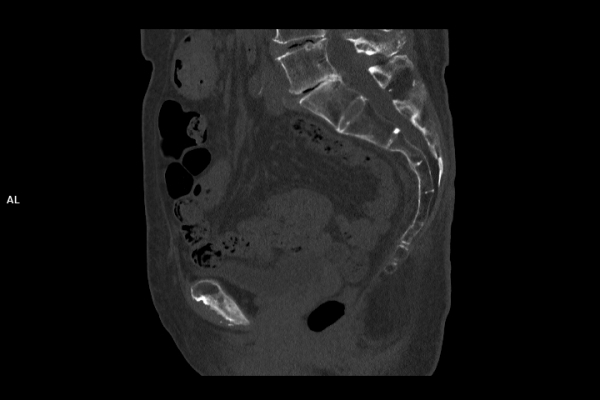

CT Untersuchung Bild

Wir verbinden modernste Medizin mit einer Atmosphäre, in der Sie sich sicher und gut aufgehoben fühlen. Klare Abläufe, Ruhe und Zeit für Sie stehen im Mittelpunkt jeder Untersuchung. CT- und MRT-Bilder ohne Wartezeit. Mit Photon-Counting-CT und 3-Tesla-MRT setzen wir auf in Kärnten einzigartige Technologien für außergewöhnlich detailreiche Bilder und besonders präzise Diagnosen. Die schonenden Verfahren eignen sich auch für Kinder und Jugendliche. Kurze Messzeiten, große offene Geräte und ein ruhiges Umfeld sorgen für eine angenehme Untersuchung und ein gutes Gefühl von Anfang bis Ende.

Die MRT (Magnetresonanztomographie) arbeitet mit Magnetfeldern und Radiowellen und eignet sich besonders für Untersuchungen der Weichteile wie Gehirn, Muskeln oder Gelenke. Die CT (Computertomographie) nutzt Röntgenstrahlen und liefert schnelle, hochauflösende Bilder, insbesondere für Knochen, Lunge oder innere Organe. Die Wahl der jeweiligen Untersuchung richtet sich an das individuelle Krankheitsbild und wird bei der Überweisung festgelegt.